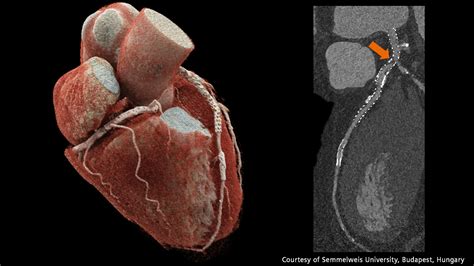

When it comes to diagnosing heart conditions, precision is paramount. A Cardiac CT, also known as a coronary computed tomography angiography (CCTA), has revolutionized the way medical professionals visualize the complex structures of the heart. By utilizing advanced X-ray technology coupled with powerful computers, this non-invasive diagnostic tool creates detailed, three-dimensional images of your heart, its arteries, and the surrounding tissues. Whether you are experiencing unexplained chest pain or have known risk factors for cardiovascular disease, understanding how this procedure works can help alleviate anxiety and prepare you for your medical journey.

At its core, a Cardiac CT scan is an imaging test that allows cardiologists and radiologists to see if your coronary arteries are narrowed or blocked by plaque buildup—a condition known as atherosclerosis. Unlike traditional stress tests, which provide functional information about how your heart handles exertion, a cardiac CT provides anatomical information. It captures images of the heart while it is beating, using sophisticated gating technology to synchronize the image acquisition with your heart rhythm.

This technology is particularly effective at identifying early-stage heart disease before symptoms manifest. By visualizing the calcified and non-calcified plaque within the arterial walls, physicians can initiate preventative treatments far earlier than previously possible.

Once the scan is complete, the images are sent to a radiologist or a specialized cardiologist who analyzes the anatomy of your coronary arteries. They will look for the presence and extent of plaque, the degree of arterial narrowing (stenosis), and the presence of any calcium deposits. You will receive a formal report, and your primary doctor will discuss the findings with you to determine the next steps in your care plan. Depending on the findings, these steps may include lifestyle modifications, cholesterol-lowering medication, or further diagnostic testing.